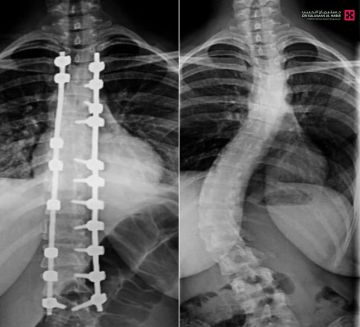

تمكّن فريق طبي في مستشفى الدكتور سليمان الحبيب بالصحافة، من إجراء عملية نوعية ناجحة لتقويم تشوّه متطور بالعمود الفقري لشابة عشرينية، كانت تعاني من ميلان (جنف) بدرجة '55' وتحدّب صدري بمقدار '70' درجة، ما سبّب لها صعوبات في الجلوس والمشي بشكل مستقيم، وأثّر سلبًا على حياتها الاجتماعية والنفسية، ذكر ذلك د. تركي العنزي استشاري المخ والأعصاب وجراحات العمود الفقري المعقّدة، رئيس الفريق الطبي المعالج.

وأوضح د. العنزي أن المراجعة خضعت فور وصولها للمستشفى لفحوصات دقيقة، شملت الأشعة السينية والرنين المغناطيسي، والتي أظهرت وجود ميلان وتحدب متزايد يتطلب تدخلاً جراحيًا عاجلًا.

وأضاف أن العملية استغرقت '5' ساعات، وأُجريت تحت المراقبة العصبية الدقيقة، وشملت تصحيح العمود الفقري على امتداد '12' فقرة عبر تثبيتها ودمجها باستخدام أحدث أنظمة التثبيت الجراحي، مع إغلاق تجميلي للجرح بتقنيات متقدمة تضمن تقليل الآثار مستقبلاً، إضافة إلى إعادة توازن الكتفين وتناسق الخصر، وأسهم في نجاح العملية توفّر أحدث الأجهزة الطبية وكوادر طبية وتمريضية عالية التأهيل.

وبيّن د. العنزي أن المراجعة بدأت بالمشي صباح اليوم التالي للجراحة، وغادرت وحدة العناية المركزة بعد تحسن ملحوظ، حيث زاد طولها بما لا يقل عن '10' سم نتيجة تصحيح الانحناء.